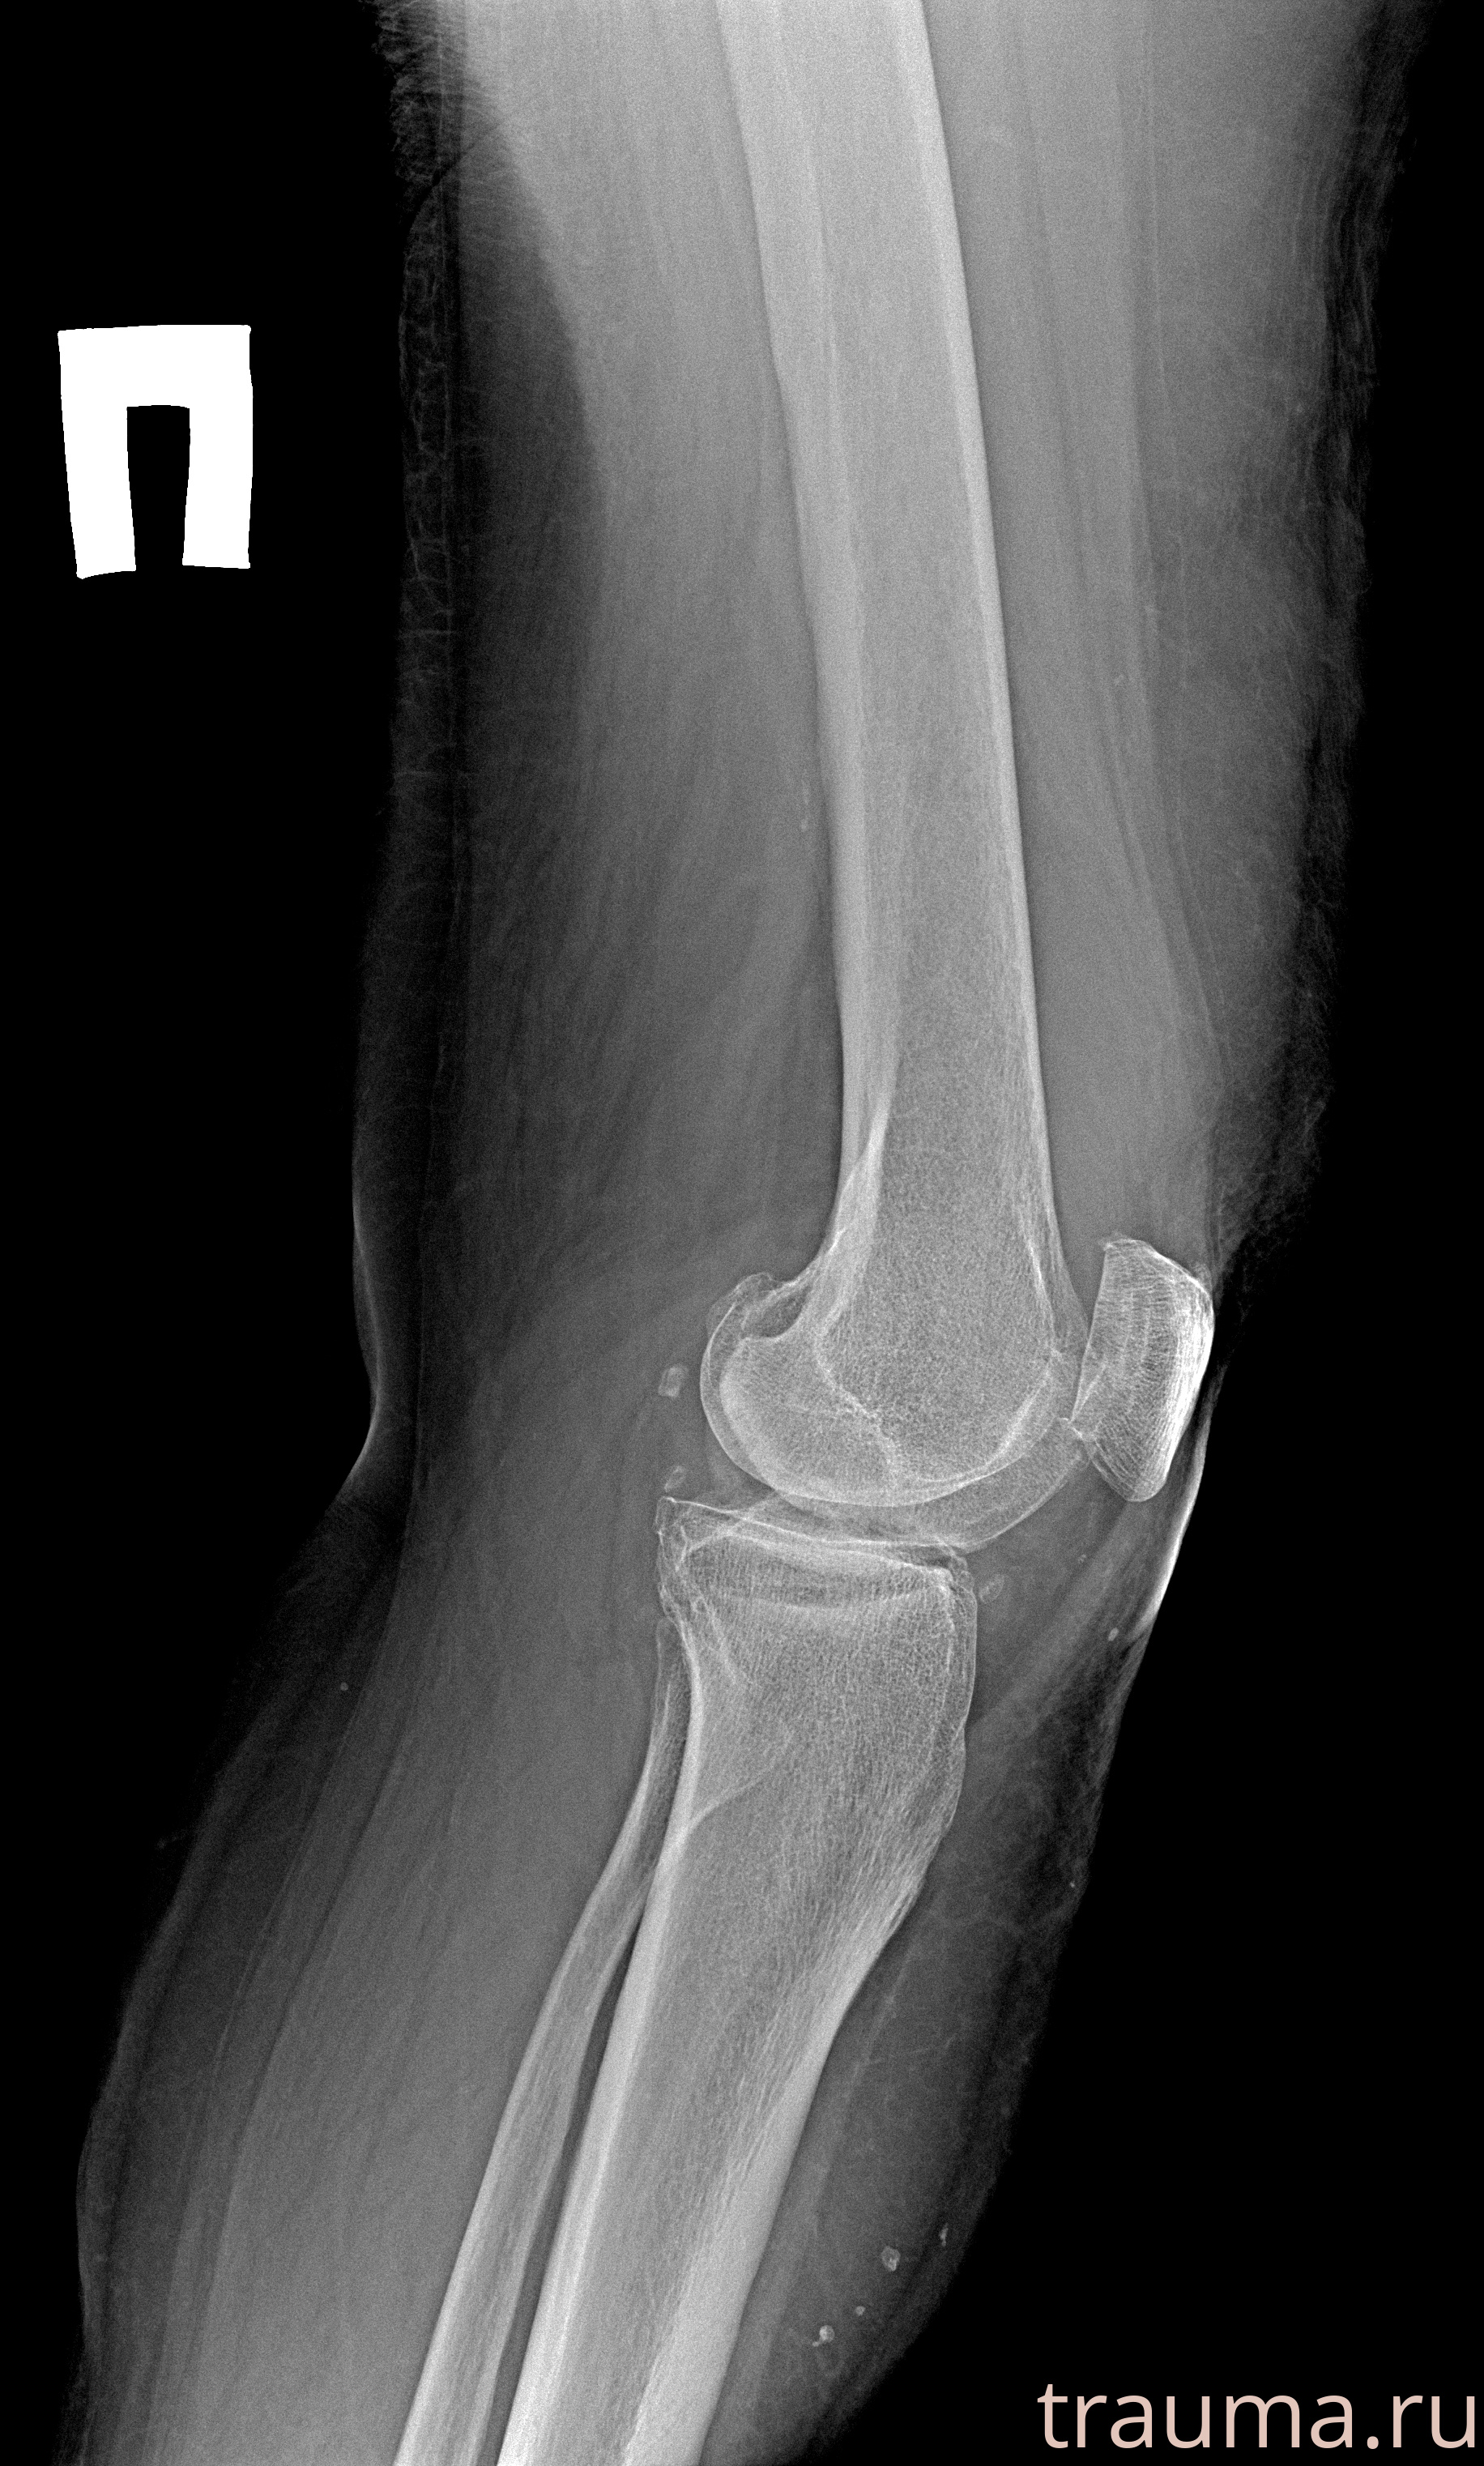

Рентгенограммы

Рентген на дому: по вашему адресу приезжает врач-рентгенолог, травматолог-ортопед с мобильным рентгеновским аппаратом, проводит диагностику травмы или заболевания, делает необходимые рентгенограммы, дает рекомендации по дальнейшему лечению. Получить качественные снимки в домашних условиях возможно благодаря уникальной методике, разработанной МосРентген Центром для института  Склифосовского